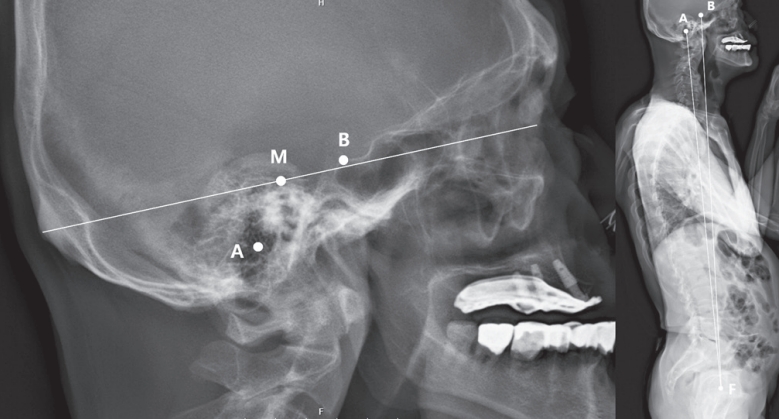

1,2) 외이도(external auditory meatus, EAM)는 MNI의 근사값으로서 두개 중심의 기준점으로 널리 사용되어 왔으나, 방사선 영상에서의 명확성과 일관성이 저하되는 경우가 많다. 이는 주로 확산된 유양돌기 공기세포(mastoid air cells)와 측면 영상에서의 중복(double contour) 현상으로 인해 발생한다(

Fig. 1). 반면, 터기 안장(sella turcica) 은 단일 중심 구조로서 대부분의 경우에서 주변 해부학적 구조에 의해 가려지지 않고 명확히 확인 가능하다. 아직까지 방사선 영상에서의 외이도의 신뢰도에 대해 평가한 연구는 많지 않다. 본 연구에서는 외이도의 방사선학적 가시성과 MNI와의 공간적 관계를 분석함으로써, 두개 중심의 기준점으로서의 신뢰성을 검증하고, 이를 터기 안장과 비교하고자 한다.

Fig. 1.수술 전 전신 척추 방사선 영상에서 촬영된 다양한 환자의 두부 영상 예시들이다. 흰색 화살표는 터기 안장(sella turcica)의 후방 경각을, 점선 원은 외이도(external auditort meatus)를 각각 나타낸다. 대부분의 환자에서 터기 안장은 명확하고 단일한 구조로 관찰되는 반면, 외이도는 불명확하거나 이중으로 나타내는 경우가 많다.

Fig. 2.비근점-후두용기 선의 중간점(MNI), 외이도, 그리고 터기 안장 사이의 평균적인 공간적 관계를 나타낸 그림. A: 외이도(EAM)m B: 터기 안장의 후방 경각, M: 비근점-후두융기 선의 중간점, F: 대퇴골두 중심. 외이도는 MNI와 수평적으로 더 가까운 반면, 터기 안장은 MNI와 수평적으로 조금 더 앞에 있었다. 터기 안장은 외이도에 비해 대퇴골두 중심과 각도적으로 더 앞에 있었다.